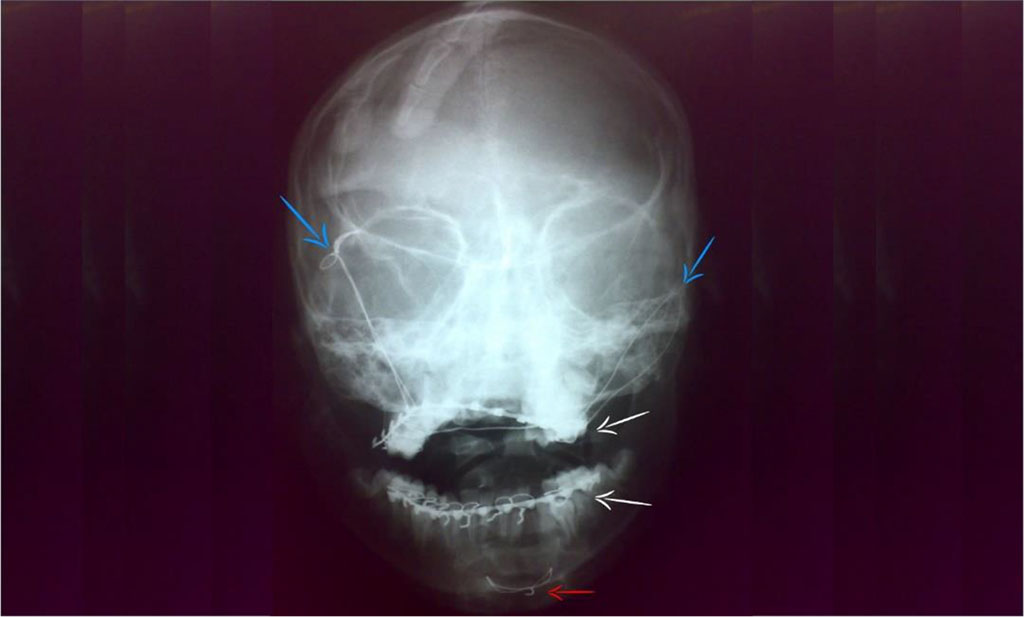

Postoperatively: the patient started oral feeding after three hours; fluids then semisolids. No fever. Pain was controlled by PerfalganTM infusion. Plain skull x-rays (Town and lateral views) revealed proper reduction, optimal mandibular occlusion without any complications e.g., malunion or non-union [Figure 6,7]. The patient was discharged on the fifth day.

Figure 7: Postoperative plain skull x-ray (Town view); Frontal suspension (blue arrows), Manduiblo-maxillary fixation (white arrows) and interosseus wire (red arrow).

During sort-term follow-up; the patient showed no complains or complications. The sutures were removed after ten days. The frontal suspension, trans-maxillary wire and arch bars were removed after one month, while the interosseous wire was not removed [Figure 7]. The patient was referred to a pediatric orthodontist for further follow-up.